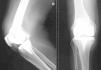

Desde las 48h del ingreso, el paciente se mantuvo afebril y con mejoría de la clínica articular. Se continuó el tratamiento antibiótico pautado durante 14 días; después de este tiempo, se le retiró la gentamicina y se mantuvo la ampicilina. Tras 28 días de ingreso se procedió a la retirada de la prótesis por parte del Servicio de Traumatología y se dejó un espaciador (spacer) de cemento (figura 2) impregnado en gentamicina durante 6 semanas; durante éstas se mantuvo el tratamiento con ampicilina intravenosa. Pasado este tiempo se implantó una nueva prótesis sin incidencias. Los cultivos intraoperatorios fueron negativos en todo momento, al igual que los hemocultivos de control. La evolución tras la cirugía fue buena y el paciente se mantuvo estable y afebril.

Figura 2. Implante de espaciador de cemento impregnado en gentamicina.